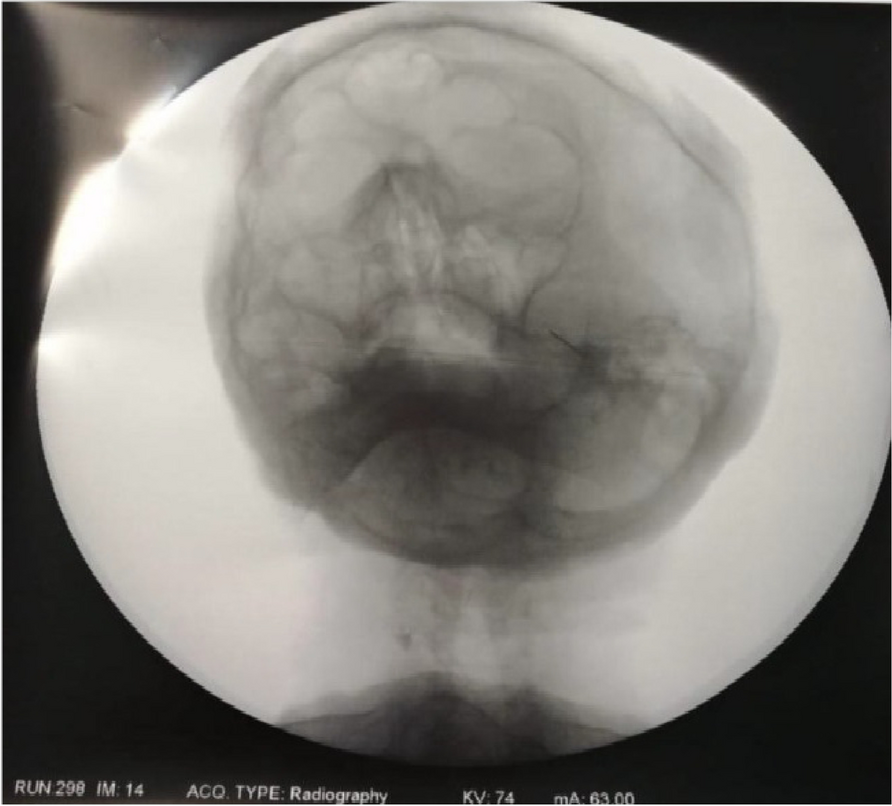

A few hours after the admission in ICU he reported a blunt abdominal pain, mainly on the right side, nausea and the exams showed increased amylase levels, urologists excluded any surgical involvement of pancreatic tissue and suspected a transient sphincter of Oddi dysfunction [3]. After one night in ICU he was transferred to the urology ward due to his clinical stability, even though Amylase peaked at 2340 U/l. Two days later abdominal pain increased to severe, with characteristics of peritonism and increased inflammatory markers. An abdomen-thorax CT scan revealed acute pancreatitis (AP) (Figure 1) and he was transferred to ICU. He started a standard treatment for acute pancreatitis and antibiotic therapy [4].

In fact, Propofol is listed as a possible cause of AP, class Ib, based on the classification of Badalov et al. [7]. Following the scheme proposed by the systematic review by Haffar et al for Propofol induced AP [6] we could confirm that our hypothesis is plausible. He satisfied the American College of Gastroenterology criteria for AP [8,9] and it is classified as severe acute pancreatitis according to the Revised Atlanta Classification with peripancreatic necrotic fluid collection [10]. Marshall score [11] after admission was two and Naranjo et al [12] probability scale for drug adverse reaction was three, meaning that the adverse reaction is possible. Latence according to Badalov et al [7] has been short or intermediate. Exclusion of other plausible causes, timing of pancreatitis symptoms and previous cases in literature support our hypothesis of propofol induced pancreatitis.

Fig. 1 (abstract A21).

See text for description